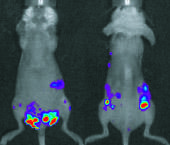

Optical imaging is based on detection of fluorescence and/or bioluminescence signal. It is a minimal- to non-invasive technique that enables the visualization of cancer cells in vivo, and can be used to follow disease progression in the animals over time to quantify the cancer burden. Bioluminescence imaging (BLI) is based on the expression of luciferase reporter gene in engineered cells.

IVIS Spectrum is an optical imaging system for small animals. The system detects photons in the visible range and is highly sensitive. The imager has space for 5 mice simultanously and each scan can take up to a minute, maximizing the amount of specimens in pre-clinical studies.